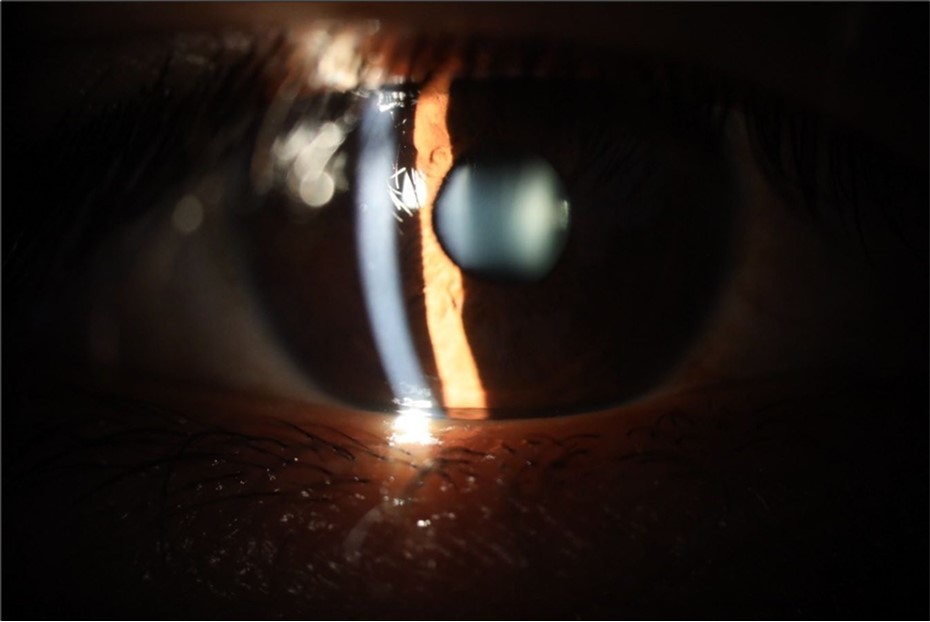

Figure 5.The slit-lamp photograph shows the anterior segment, relatively unscathed, in terms of transparent media (Cornea, crystalline and vitreous).

Figure 6.Slit-lamp examination showed a solution of continuity in the left temporal region, which fortunately only affected the conjunctiva and Tenon's capsule, while the sclera was unscathed.

Figure 15.The photograph shows better specular reflection, compared to the first day of the exam.

Figure 16.The anterior segment of the right eye shows the vitreous with greater transparency. The cornea and lens, as well as the anterior chamber, are in good condition.